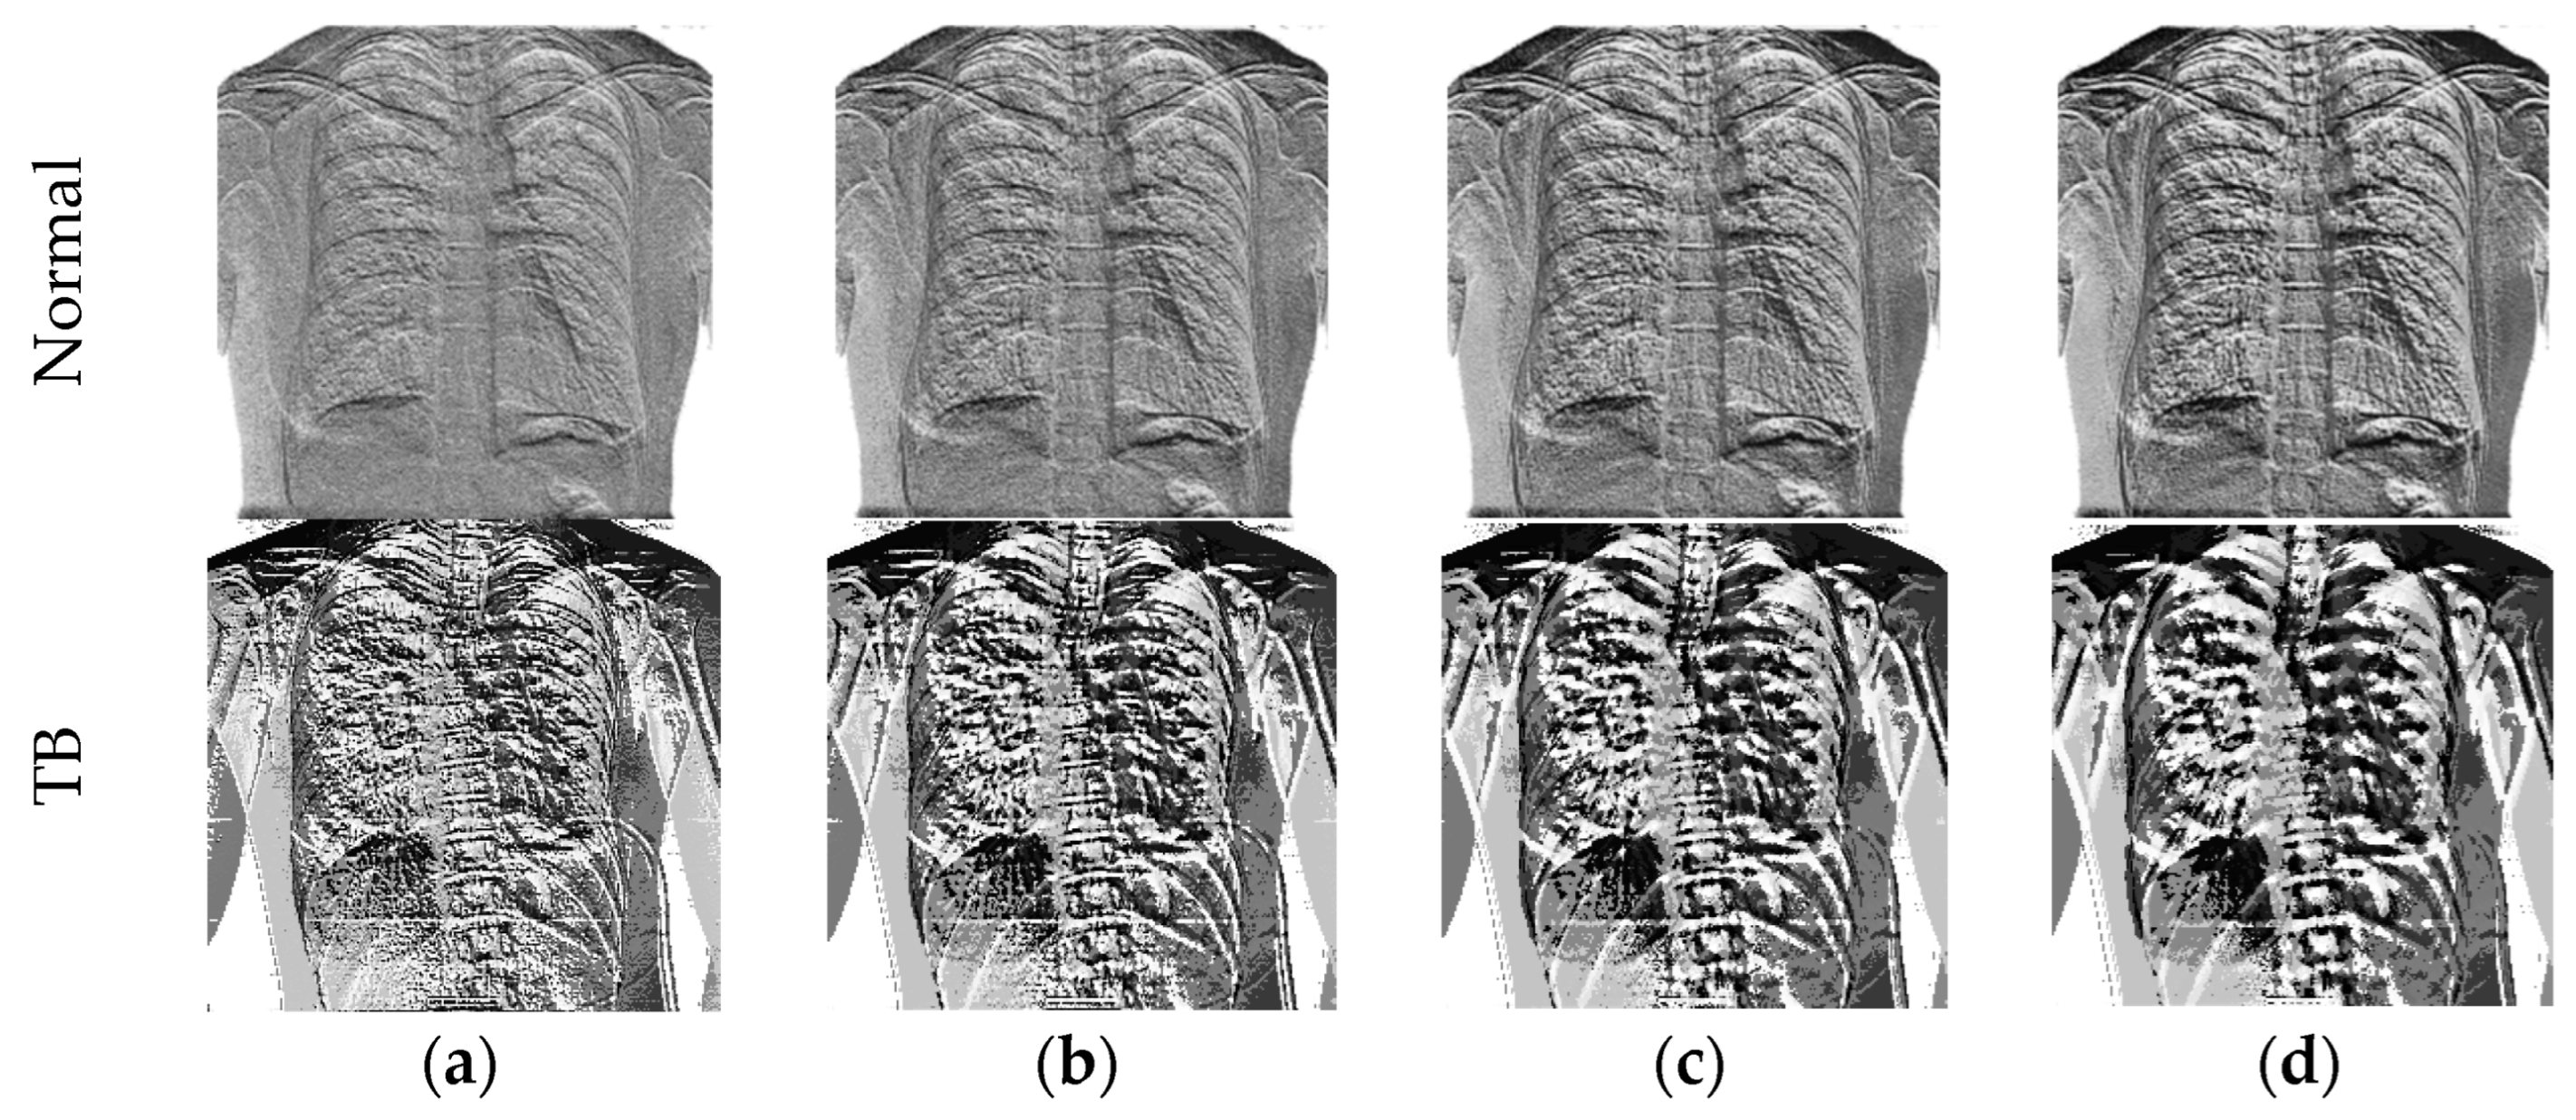

3.3.2. Machine-Learning-Features